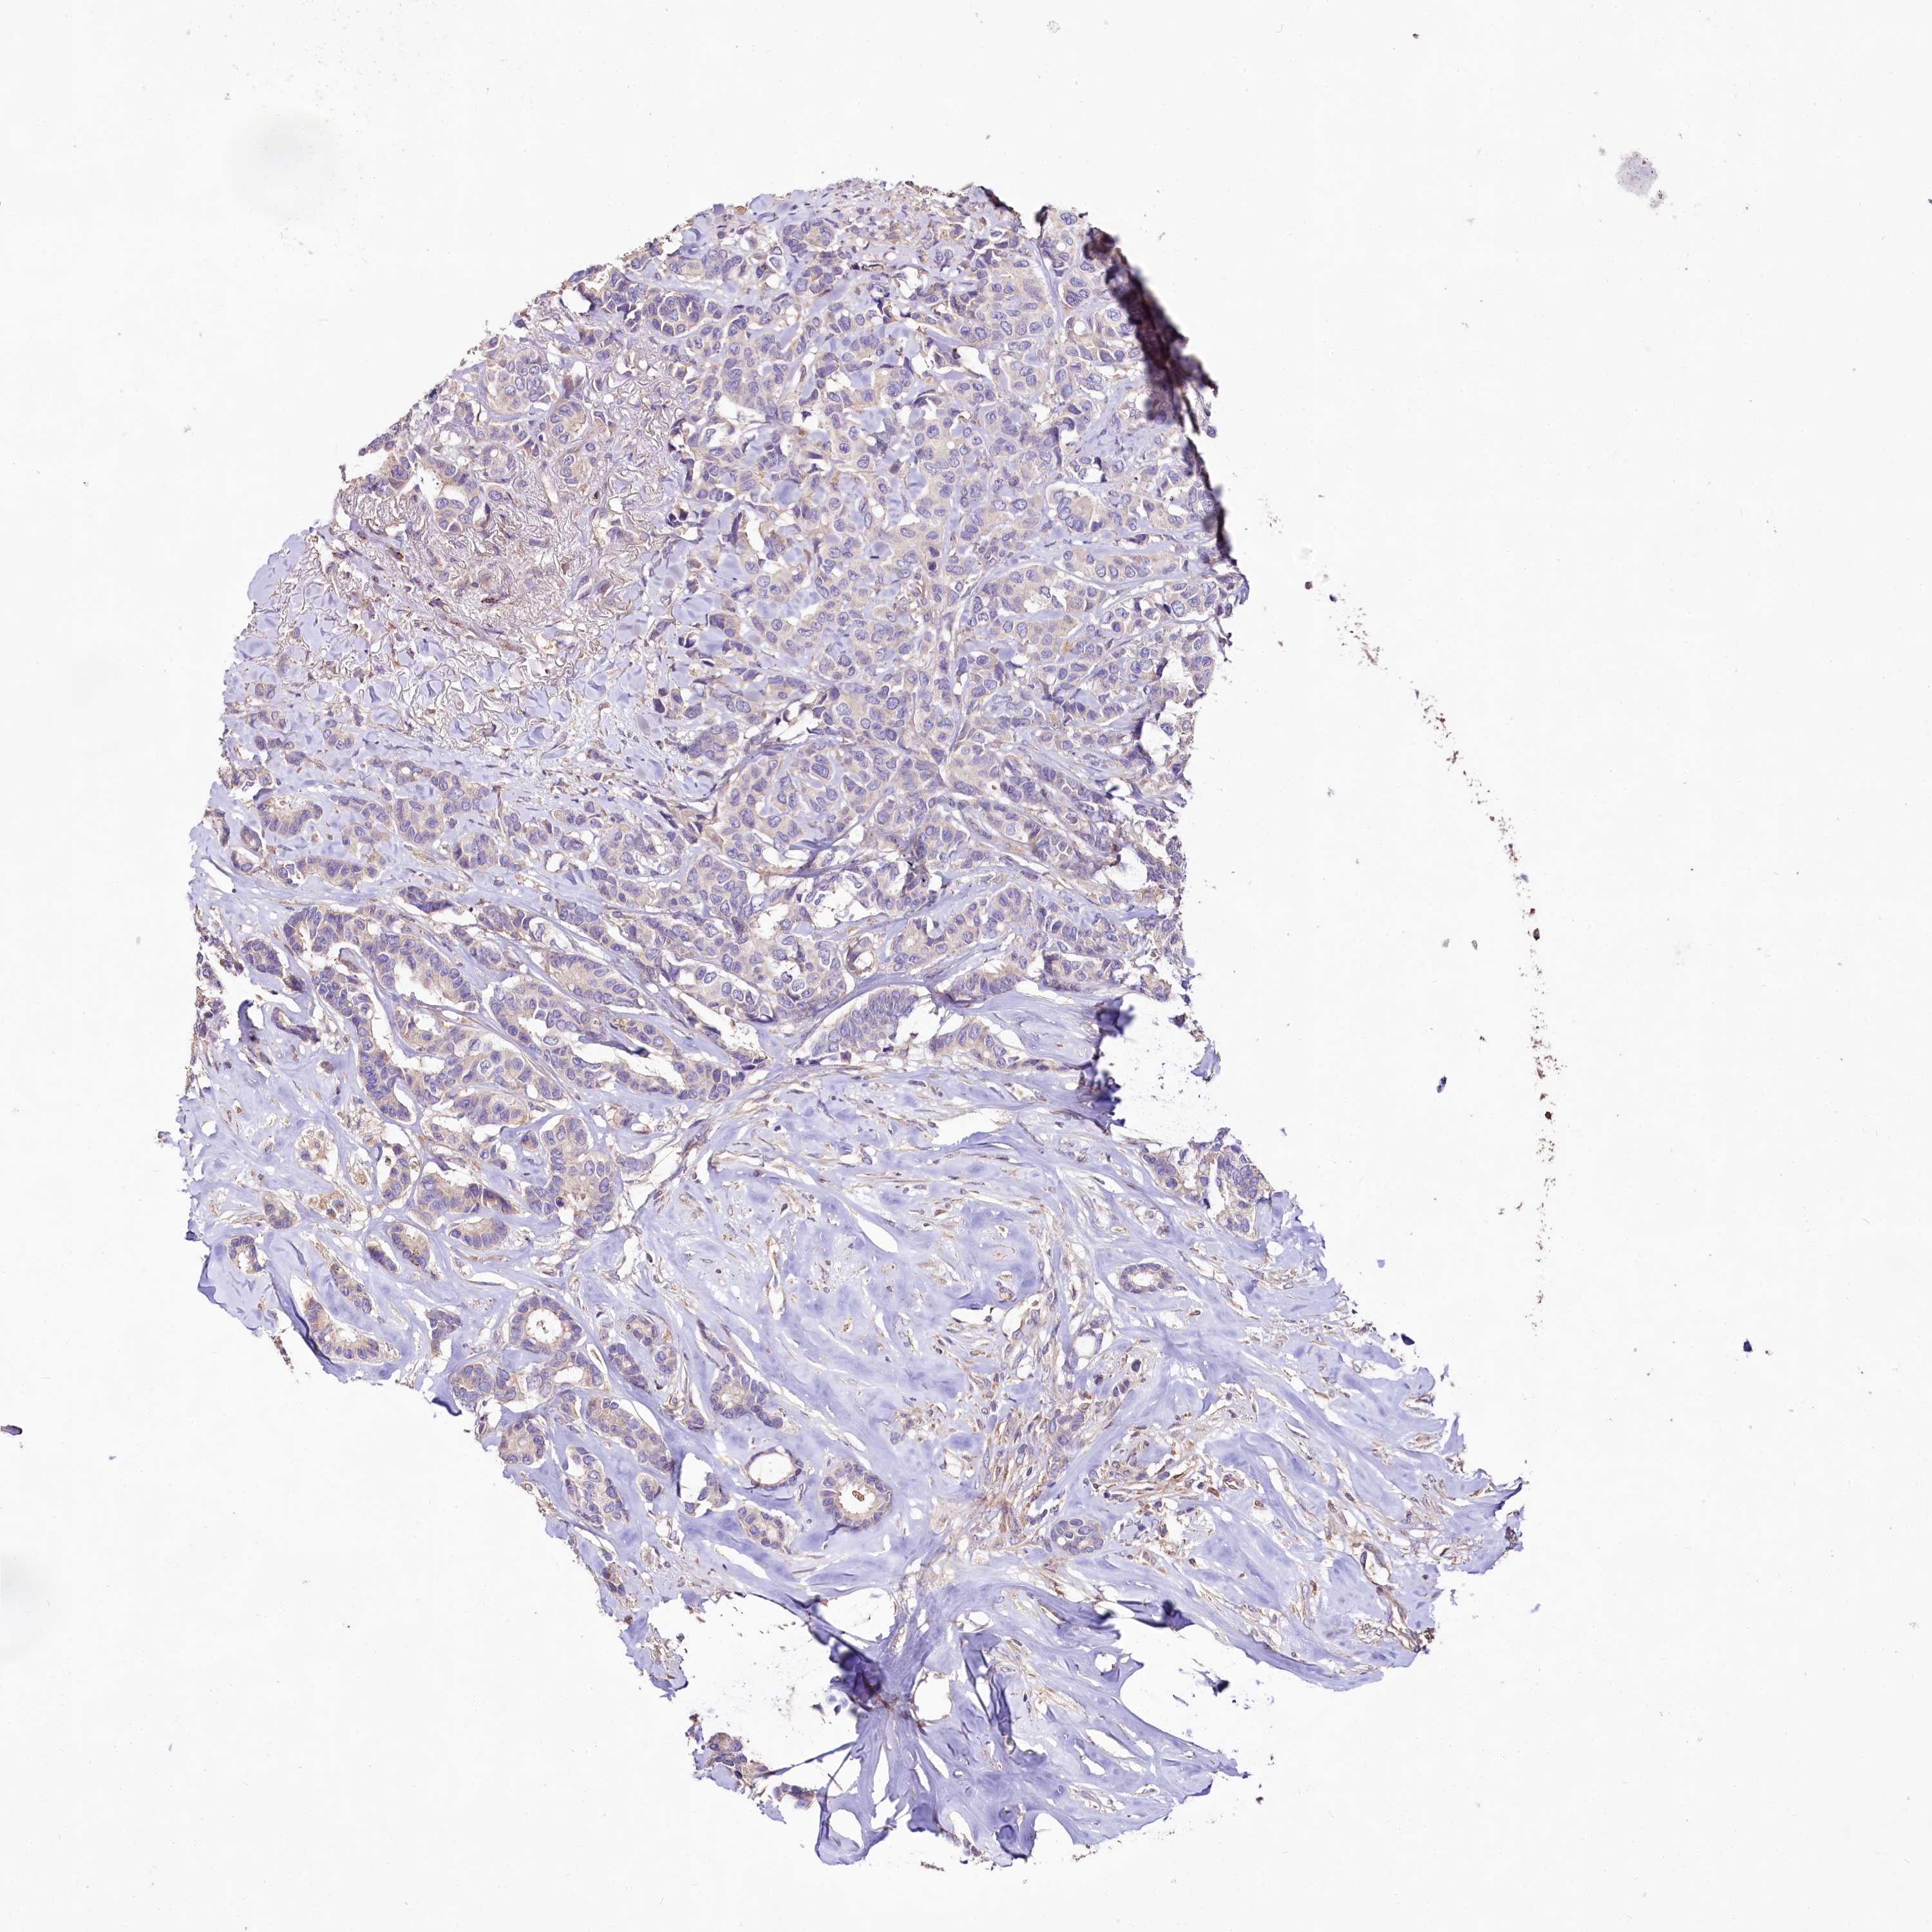

BRCA TCGA BRCA VALIDATION PROTEIN EXPRESSION

ANTIBODIES

AND

VALIDATION